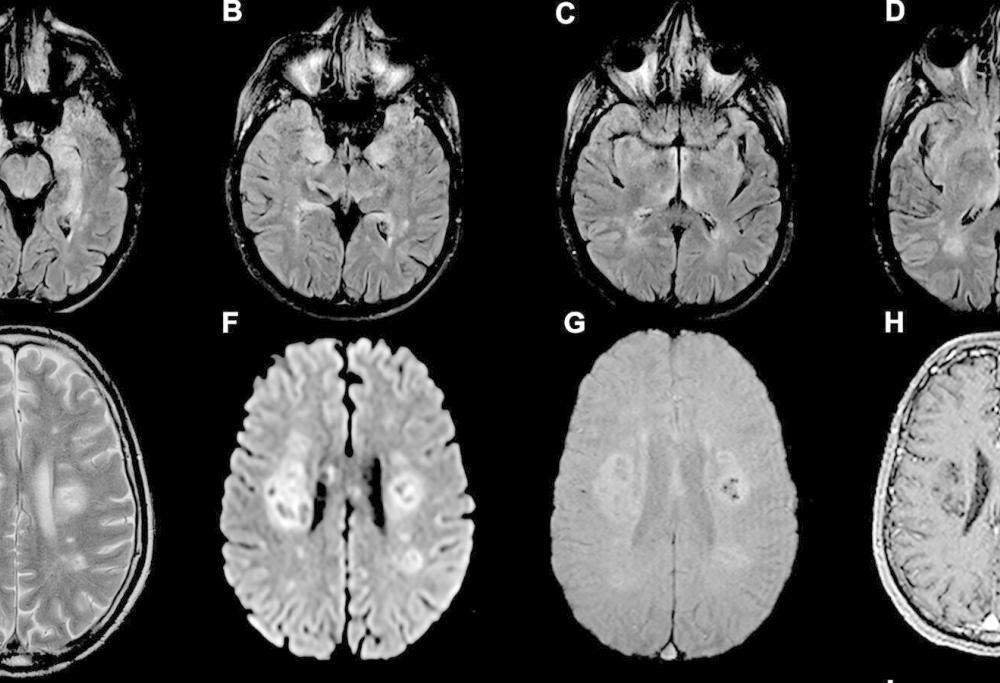

Un recente studio (intitolato “Neuroinvasion of Sars-CoV-2 in human and mouse brain“) condotto da ricercatori inglesi e pubblicato su Brain ha lavorato sull’imaging cerebrale e sui sintomi del paziente per analizzare le possibili ripercussioni del coronavirus sul cervello. La ricerca è stata poi rielaborata e ampliata grazie ad esperimenti sui topi e ad analisi del tessuto cerebrale dei morti con coronavirus.

Secondo questo studio il Covid-19, oltre a comportare cambiamenti metabolici, colpirebbe diversi organi, arrivando al cervello e al sistema nervoso centrale attraverso il bulbo olfattivo, gli occhi o dal flusso sanguigno.

Una volta invase le cellule cerebrali, pare che il virus sia in grado di moltiplicarsi facendo morire le altre cellule: questo tipo di infezione potrebbe essere legata a fattori genetici e alla carica virale del virus. Inoltre, a differenza di altri virus, non innescherebbe una risposta immunitaria per contrastare l’infezione nel cervello.